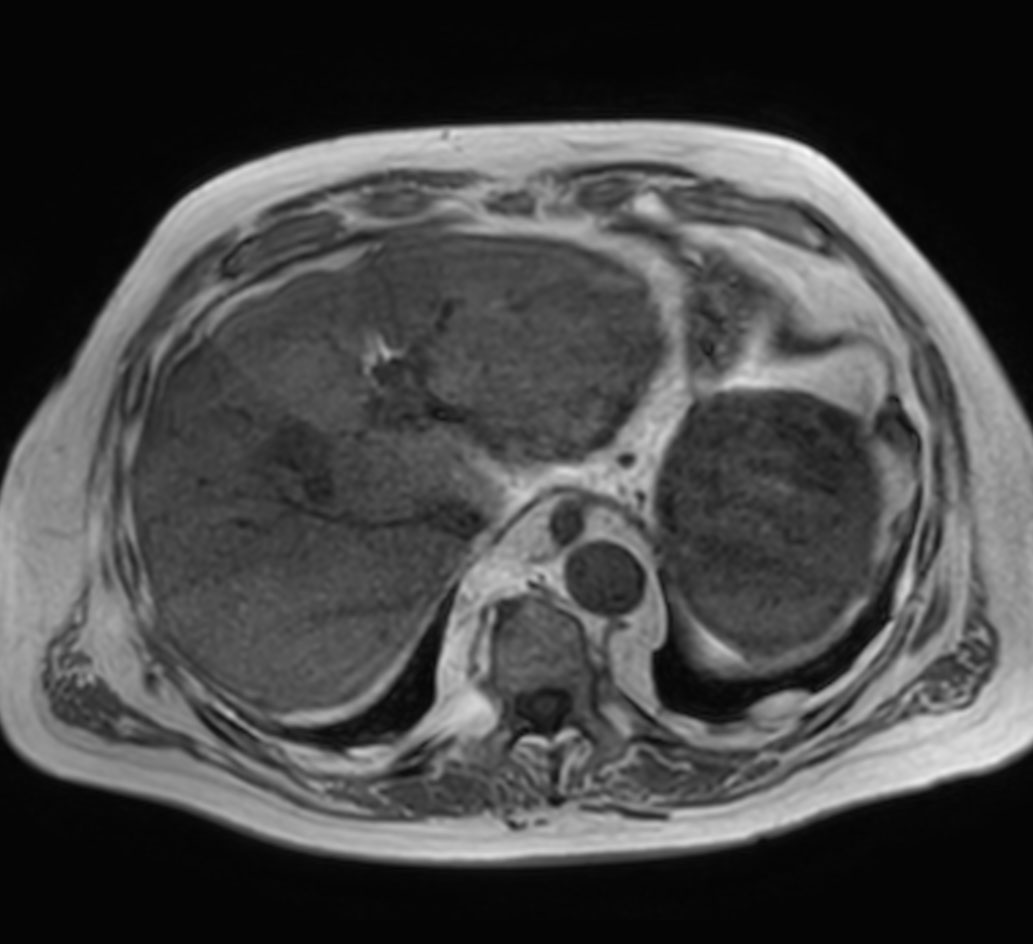

Axial T1w mDIXON XD (Water only)